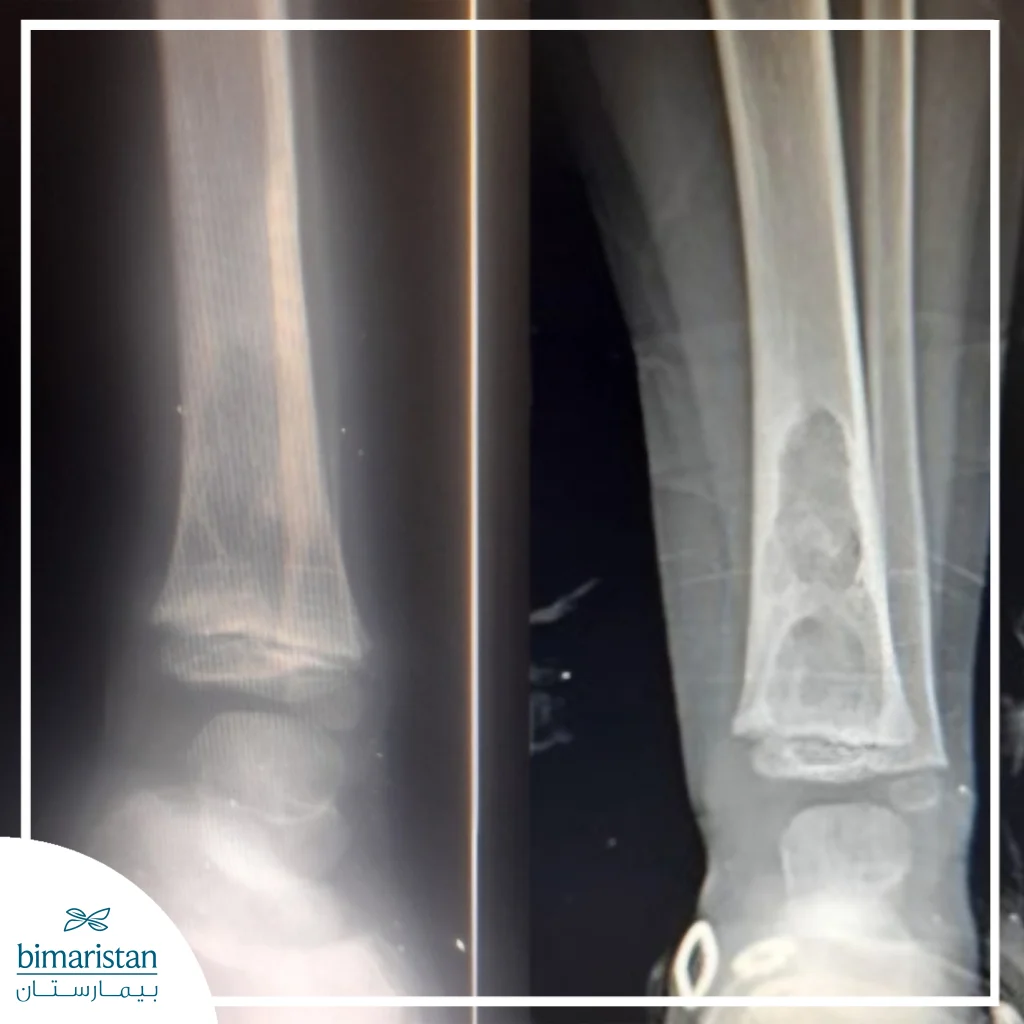

2. السل العظمي أو المفصلي

يمثّل السلّ العظمي ثاني أكثر أشكال السل خارج الرئة شيوعاً، ويحدث عندما تصل الجرثومة إلى العظام أو المفاصل عبر مجرى الدم من بؤرة رئوية سابقة. يُصيب المرض عادة العمود الفقري في الفقرات الصدرية أو القَطَنية، ويُعرف هذا الشكل باسم مرض بوت. تبدأ الإصابة بآلام مزمنة في الظهر أو المفصل المصاب تزداد تدريجياً مع الوقت، وقد يلاحظ المريض تيبّساً في الحركة أو تورماً في المنطقة، ومع تدهور الحالة قد يحدث تشوّه في العمود الفقري أو انضغاط على الأعصاب الشوكية يؤدي إلى ضعف أو شلل في الأطراف السفلية.

في المفاصل، يظهر المرض بشكل التهاب مزمن بطيء التطور يُصيب غالباً مفصل الورك أو الركبة، مسبباً ألماً متقطعاً وتورماً خفيفاً يزداد مع الحركة. يتصف هذا الشكل من السل بمساره الطويل والأعراض غير الواضحة في بدايته، وغالباً ما يُشخّص بعد مرور أشهر من بدء الأعراض بسبب غياب العلامات المميزة في المراحل الأولى.

تُسهم وسائل التصوير الحديثة مثل الأشعة المقطعية والتصوير بالرنين المغناطيسي في تحديد موضع الإصابة بدقة، وتُظهر المظاهر النموذجية لكل عضو؛ كالعقيدات الدقيقة في الرئتين بالسل الدخني أو الخراجات الباردة في العمود الفقري بمرض بوت، وفي حال الاشتباه بالسل المنتشر رغم سلبية الفحوص، قد تُجرى خزعة من الكبد أو نقي العظم لتأكيد التشخيص.